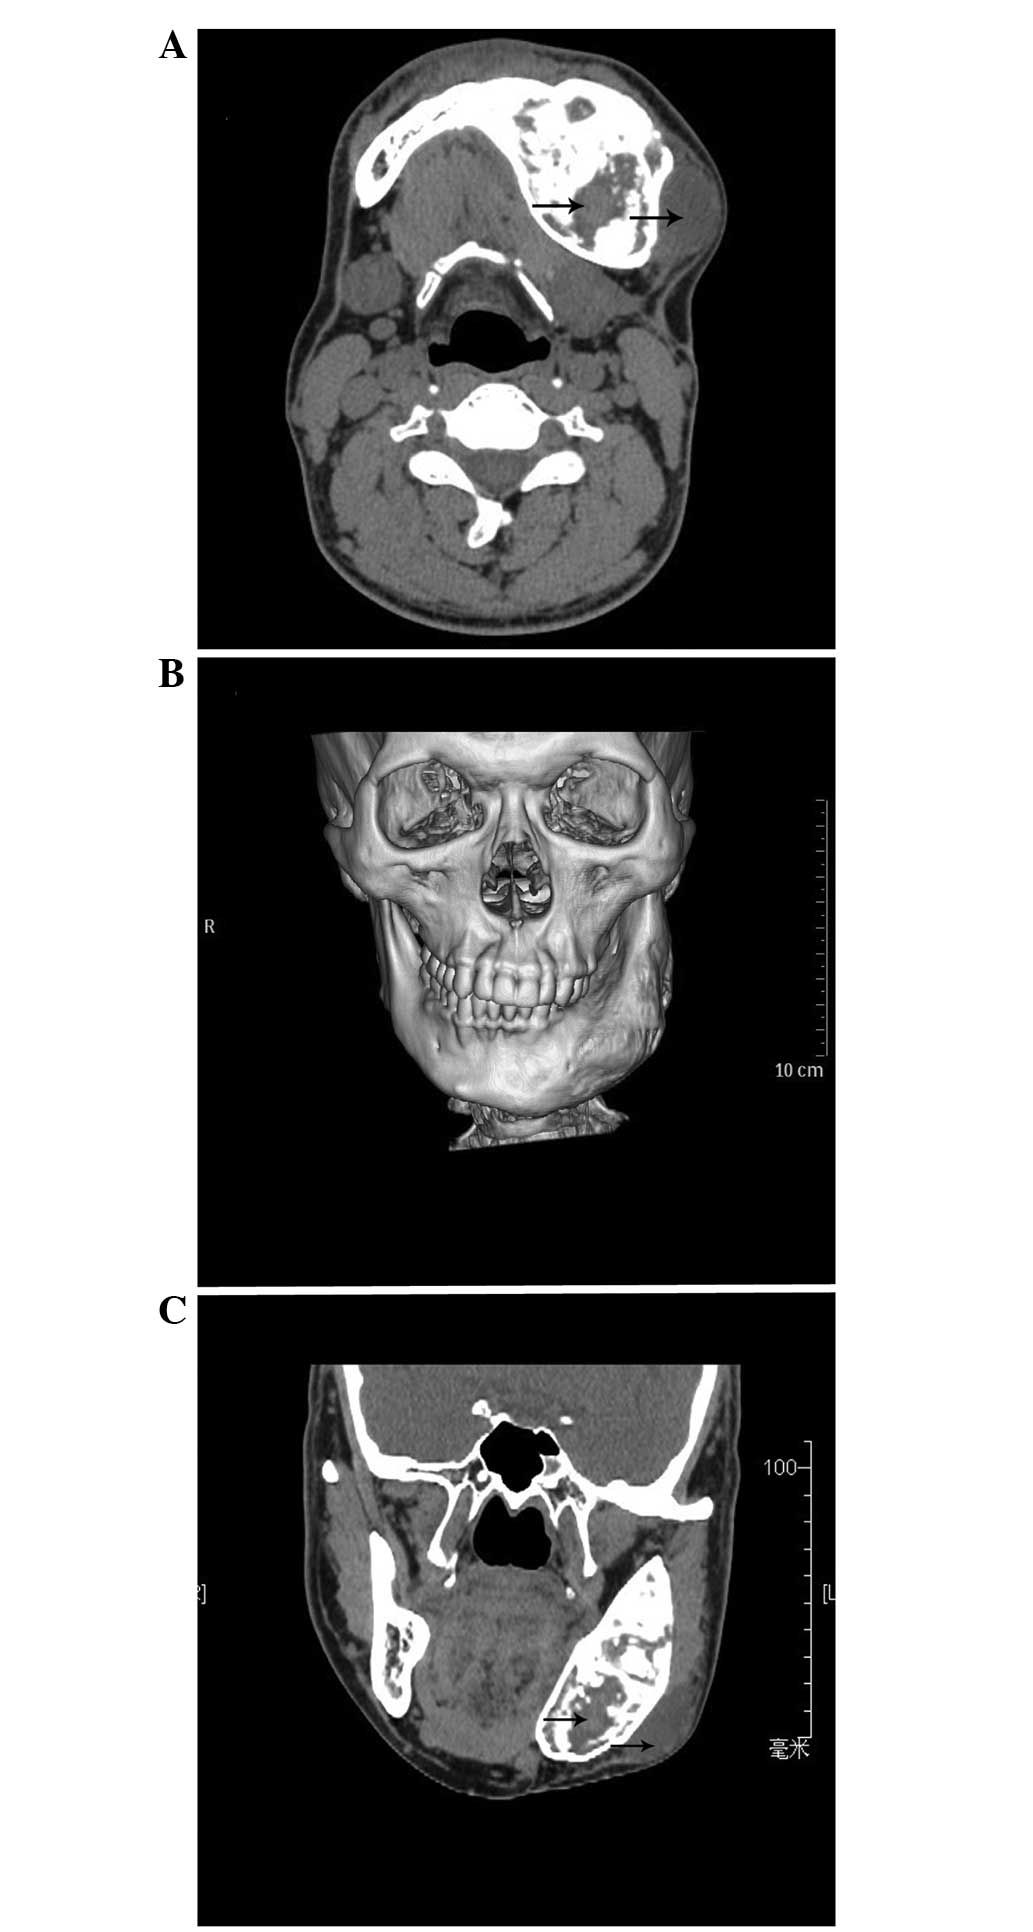

Monosotic fibrous dysplasia and solitary intramuscular myxoma of the head and neck: A unique presentation of Mazabraud's syndrome and a literature review

Mazabraud's syndrome (MS) is a rare disease that is a combination of fibrous dysplasia and intramuscular myxomas. MS is a benign lesion and there is little data on the disease due to its low incidence. In the present study, the case of a 38‑year‑old patient who presented with a soft‑tissue mass involving the masseter and swelling at the mandibular body and mandibular ramus is reported. Since the mandible is an important aesthetic and functional organ in the oral and maxillofacial region, surgery was primarily aimed at resecting the tumor, with good safety margins, and reconstructing the resultant defect. The lesions were pathologically diagnosed as MS. The unique features of this case included the painless and monostotic fibrous dysplasia, the solitary intramuscular myxomas involving the jaw and the male gender of the patient. MS usually occurs in the lower extremities, with an unusual predilection for the right limb; however, it rarely occurs in the head and neck region. A retrospective analysis of the clinical features and management of MS was also performed in the present study, together with a literature review. From the literature, it was concluded that the incidence of MS is ~2.3‑fold greater in female patients than in male patients, and that the age of onset of MS ranges between 17 and 82 years, with an average age of 46.25 years.

Figure 1